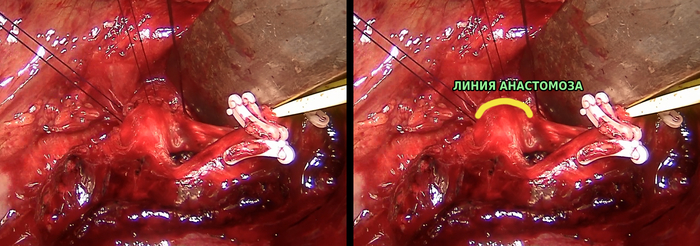

Выше я писал, что опухоль расположена в верхнедолевом бронхе и переходит на главный бронх, следовательно, для обеспечения радикальности операции нам нужно резецировать главный бронх. Раньше в таких случаях выполняли пневмонэктомию - удаление всего лёгкого, ведь поражен главный бронх, и обеспечить радикальность операции, то есть гарантию удаления всего опухолевого объема, можно было только так. Но ведь нижняя доля лёгкого совершенно здорова, и очень жалко ее терять из-за какого-там пятимиллиметрового перехода опухоли на главный бронх. Именно для таких случаев разработаны схемы бронхопластических операций. При таких операциях мы отсекаем пораженную долю, отсекаем циркулярный фрагмент главного бронха на достаточном расстоянии от края опухоли, а его (главного бронха) остаток вшиваем в здоровый нижнедолевой бронх, как труба в трубу. Тем самым обеспечивается и радикальность операции и сохраняется целая половина легкого.

Сформированное соединение между различными структурами называется анастомоз. Анастомоз может быть сосудистым (сшивают два сосуда), кишечным (сшивают кишку с кишкой), пищеводно-желудочным (сшивают пищевод и желудок) и так далее. В данной операции мы формируем межбронхиальный анастомоз при помощи рассасывающейся нити

Схематически операция выглядит вот так:

План операции составлен, осталось самое простое - сделать. К сожалению, это большая открытая операция, в течение которой не всегда есть возможность фиксировать этапы ее выполнения, а уж тем более делать красивые фотки. За качество и непонятность некоторых фото прошу прощения.

Главный и нижнедолевой бронхи. Главный смотри на нас, мы хорошо видим его просвет. Нижнедолевой бронх смотрит от нас:

Сводим края анастомоза и сшиваем хитрым швом, не забывая путаться в нитях:

Наступает момент, когда анастомоз полностью сформирован:

Всё. Мы удалили верхнюю долю левого лёгкого, сделали циркулярную резекцию главного бронха и сформировали межбронхиальный анастомоз.

Проходит неделя, пока делать контрольную бронхоскопию, на которой мы видим циркулярный анастомоз,  (красная полоска с небольшими синяками по окружности бронха). Анастомоз полностью проходим, состоятелен: